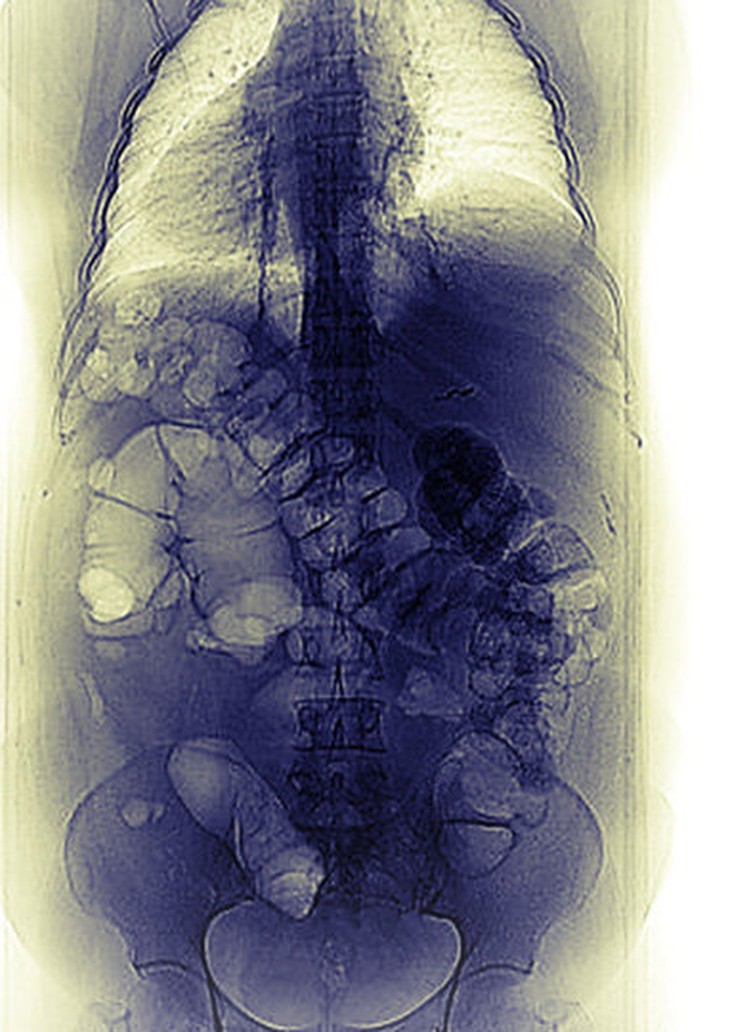

TTCT - Hiện tượng một phần hay toàn bộ nội tạng bẩm sinh đảo ngược vị trí bên trong cơ thể đã được phát hiện từ hơn hai thế kỷ trước. Dù vẫn còn những bí mật chưa được khoa học giải mã thấu đáo, nhưng gần đây hiện tượng này đang mở ngỏ nhiều cánh cửa khám phá lý thú. Một ngày năm 1788, các sinh viên Trường y khoa Hunterian ở London (Anh) đang mổ một tử thi thì phát hiện chuyện lạ lùng: nội tạng của xác chết đối nghịch với người bình thường. Thay vì ở bên phải, lá gan lại nằm bên trái. Và trái tim thay vì nằm bên trái lại ở bên phải. Các sinh viên tìm gặp GS Matthew Baillie và thầy cũng kinh ngạc như trò. Sau này GS Baillie viết: “Trường hợp này cực kỳ hiếm thấy, kể cả với những nhà giải phẫu học danh tiếng nhất”. Đó là phát hiện đầu tiên trong y học về tình trạng situs inversus (toàn bộ nội tạng đảo ngược). Chỉ cần một máy động là đảo lộn! Nhưng làm cách nào phôi thai biết được vị trí trái - phải để phát triển các cơ quan nội tạng? Đó là câu hỏi mà TS sinh học Dominic P. Norris thuộc Hội đồng nghiên cứu y khoa ở Harwell (Anh) cùng nhiều nhà khoa học khác đang đi tìm giải đáp. Theo New York Times, họ đã xác định được một số bước theo đó các cơ quan của phôi thai sẽ phát triển ở bên trái hay bên phải. Những đột biến tạo ra situs inversus có thể dẫn tới nhiều rối loạn nghiêm trọng, trong đó có các khuyết tật tim bẩm sinh. Giải mã được các tác động của gen đột biến này có thể giúp tìm ra nhiều cách chẩn đoán và điều trị các rối loạn. TS Rebecca Burdine, nhà sinh học phân tử ở Princeton (Mỹ), nói: “Hiểu được cách cơ thể xác định trục trái - phải là có nhiều khả năng hiểu được bệnh tim bẩm sinh”. Cơ thể chúng ta khởi đầu phát triển đối xứng, bên trái là phản chiếu hoàn hảo của bên phải. Theo một nghiên cứu của Sudipto Roy thuộc Viện Sinh học tế bào và phân tử Singapore đăng trên tạp chí Open Biology (1) đầu tháng 6 này, những dấu hiệu về sự bất đối xứng trái - phải trong cơ thể người chỉ rõ ràng khoảng sáu tuần sau khi phôi thai phát triển. Trái tim sẽ bộc lộ dấu hiệu bất đối xứng trước tiên. Khởi đầu chỉ là một hình ống đơn giản, tim sẽ cong vòng sang trái, sau đó sẽ hình thành các cấu tạo khác nhau ở hai bên, tạo ra các ngăn và các mạch dẫn cần thiết để bơm máu. Trong khi đó, các cơ quan khác cũng bắt đầu chuyển động. Bao tử và gan từng cái một sẽ di chuyển theo chiều kim đồng hồ khỏi trục giữa của phôi thai. Ruột già sẽ nhú ra một mẩu ruột thừa ở bên phải. Lá phổi bên phải sẽ mọc ba thùy, bên trái chỉ có hai. Những thay đổi thấy rõ này chỉ nảy sinh rất lâu sau khi phôi thai đã có khả năng phân biệt trái - phải. Các thí nghiệm cho thấy phôi thai từ đầu đã tạo ra các protein khác nhau cho mỗi bên, dù trông nó vẫn đối xứng. Giới sinh học đã xác định được một điểm duy nhất nơi bắt đầu phá vỡ sự đối xứng này: một hốc lõm nhỏ xíu - gọi là node (mắt) - trên trục giữa của phôi thai. Bên trong cái mắt này được lót bằng hàng trăm sợi lông nhỏ xíu - gọi là cilia (mao) - quay tròn với tốc độ 10 lần/giây. Các mao xoay tròn này đều hướng nghiêng ra ngoài. Chính độ nghiêng này là điều cốt yếu của khả năng phân chia cơ thể thành hai bên trái - phải. Gần đây, TS Kathryn V. Anderson và các cộng sự ở Trung tâm ung thư Sloan-Kettering (Mỹ) đã thử ngắt các gen điều khiển các mao này. Theo báo cáo của họ trên tạp chí Development (2), đột biến đó đã khiến một số phôi thai chuột hình thành một cơ thể có nội tạng đảo ngược. Độ nghiêng của các mao này hết sức quan trọng vì phôi thai nằm trong một màng dịch mỏng, nếu các mao thẳng đứng thì chúng sẽ đẩy chất dịch lỏng này theo mọi hướng và sẽ không tạo ra được sự lưu chuyển nào. TS Norris giải thích: “Nó giống như cái máy trộn vậy. Cứ xoay tròn, xoay tròn”. Khi nghiêng như thế, các mao sẽ đẩy chất dịch theo một hướng từ phải sang trái. Khi các nhà khoa học đảo ngược dòng lưu chuyển này trong phôi thai chuột, kết quả là các nội tạng đảo ngược vị trí. Chỉ cần một lưu chuyển rất nhẹ về phía trái cũng đủ cho phôi thai phát triển thích hợp. Năm ngoái, các nhà khoa học ở ĐH Osaka (Nhật) báo cáo rằng chỉ cần hai sợi mao là đủ thực hiện nhiệm vụ này. Một hình chụp X-quang cho thấy cơ thể có toàn bộ nội tạng đảo ngược vị trí - Ảnh: radiopaedia.org Nhiều bí mật chưa giải đáp Một khi chất dịch bắt đầu lưu chuyển thì chỉ cần 3-4 giờ là phôi thai đã xác định rõ các vị trí trái - phải. Khoa học hiện nay vẫn chưa hiểu biết đầy đủ về các bước trung gian. Trong bước đầu tiên, chất dịch lưu chuyển trong hốc lõm ấy cho tới khi đến phía bên trái của miệng hốc. Miệng này được bọc bằng những sợi mao không xoay tròn, nhưng bằng cơ chế nào đó chưa giải thích được, các mao này vẫn phản ứng theo dòng lưu chuyển - có thể bằng cách phóng thích những nguyên tử canxi cho lan tỏa ra các tế bào xung quanh. Các tế bào này lại phản ứng bằng cách tiết ra một chất protein gọi là nodal lan về phía bên trái của phôi thai và tiếp tục tác động các tế bào khác tự tiết ra nodal, tạo thành một chu trình phản hồi khiến phía bên trái tràn ngập nodal và phía bên phải hầu như không hề có chất protein này. Giới khoa học vẫn đang tìm hiểu cơ chế nào giúp chất nodal xác định vị trí nội tạng ở hai bên cơ thể. Trong những năm gần đây, nhiều nhà nghiên cứu không tập trung vào chuột nữa mà vào loài cá ngựa vằn (zebra fish) vì loài này có lợi thế là phôi thai trong suốt. Các nhà khoa học có thể điều khiển cho các tế bào trong phôi thai cá ngựa vằn phát sáng để quan sát được các cơ quan trong quá trình hình thành. TS Burdine ở Princeton đã nghiên cứu cơ chế định hình nội tạng của chất nodal đối với tim của loài cá ngựa vằn khi các tế bào phôi thai di chuyển quanh cơ quan nội tạng này. Theo bà, dường như chất nodal trực tiếp điều khiển các tế bào phía bên trái di chuyển nhanh hơn các tế bào bên phải. Bà và nhóm cộng sự đã công bố trên số tháng 1-2013 của tạp chí PLoS Genetics (3) rằng các tế bào chuyển động nhanh ở bên trái đã lôi kéo toàn bộ trái tim theo chiều kim đồng hồ. Từ cú xoay vặn khởi động này, trái tim sau đó sẽ phát triển theo các bên trái - phải rõ rệt. Một số nghiên cứu cho rằng những tín hiệu đầu tiên này cũng tác động đến sự phát triển của não. Từ lâu, giới khoa học biết rằng hai nửa bộ não có những khác biệt quan trọng: bán cầu não phải chẳng hạn sẽ đóng vai trò lớn trong việc hiểu biết đời sống tinh thần của người khác, còn bán cầu não trái lại quan trọng đối với khả năng tập trung chú ý. Nhiều động vật có xương sống khác cũng có sự khác biệt trái - phải ở não bộ, nhưng nguồn gốc của sự bất cân xứng này gần như vẫn còn bí ẩn. “Tôi cho rằng cá ngựa vằn chính là loài có xương sống mà chúng ta hiểu biết cặn kẽ nhất” - nhà sinh học Joshua T. Gamse ở ĐH Vanderbilt (Mỹ) nhận xét. TS Gamse cùng nhiều nhà nghiên cứu khác đã phát hiện chất nodal thúc đẩy một phần nhỏ của não bộ loài cá này phát triển với hai bên trái - phải. Sự khác biệt này sau đó lan tỏa ra các phần khác của cả não bộ. Nhưng khoa học hiện vẫn chưa rõ con người và các loài có vú khác có phát triển theo cùng một cách hay không. Chắp vá lại trái tim Khi nghiên cứu các dấu hiệu sinh học này, giới khoa học cũng nghiên cứu những rối loạn có thể liên quan đến tình trạng lộn tùng phèo. Trường hợp mà GS Baillie đã mô tả năm 1788 là lạ lùng nhất, hiếm thấy nhất nhưng cũng thuộc loại vô hại nhất vì theo TS Burdine, “người ta có thể sống bình thường với cái trục đảo ngược hoàn toàn như thế, cho đến khi một bác sĩ phát hiện trái tim nằm lộn chỗ”. Tình trạng situs inversus tương đối an toàn vì mọi cơ quan nội tạng đều sắp xếp đồng bộ với nhau, dù tất cả lật ngược. Theo TS Norris, nguy cơ thật sự nằm ở những bộ phận riêng lẻ bị đảo vị trí. “Nếu trái tim nằm lộn chỗ trong khi mọi thứ khác đều đúng vị trí thì hầu như luôn luôn tai họa” - TS Burdine nói. Trong những trường hợp khác, trái tim phát triển đúng vị trí ở bên trái cơ thể nhưng cấu tạo bên trong (van tim và buồng tim) lại phát triển ngược. Những rối loạn này có thể không gây nguy hại ngay nhưng về sau có thể đòi hỏi phải giải phẫu phức tạp để sắp xếp lại trái tim. TS Burdine hi vọng việc nghiên cứu các rối loạn này sẽ dẫn đến những thí nghiệm di truyền giúp tiên liệu nguy cơ từ các khuyết tật tim tiềm ẩn này. Bà thậm chí còn hình dung một cách ứng dụng để tái tạo những trái tim đã tổn thương bằng các tế bào gốc. Theo bà, vấn đề không chỉ đơn thuần là xác định đúng tế bào mà còn phải đặt tế bào trong cấu trúc ba chiều thích hợp để kích tạo những tín hiệu chính xác nhằm điều khiển tế bào đi đúng hướng. Bà nói: “Một trong những tín hiệu đó là tín hiệu trái - phải”. Từ báo cáo khoa học của GS Matthew Baillie (1781-1823, ảnh) mô tả chi tiết đầu tiên trong y văn thế giới về tình trạng toàn bộ nội tạng đảo ngược (situs inversus), khoa học ước tính trong 20.000 người mới có một trường hợp. Trước đó, tình trạng một cơ quan nội tạng phát triển nhầm chỗ đã được biết đến. Chính danh họa Leonardo da Vinci (1452-1519) đã phát hiện trái tim nằm bên phải trong quá trình giải phẫu tử thi để nghiên cứu cơ thể học. Đến năm 1643, trường hợp này mới được nhà giải phẫu học người Ý Marco Aurelio Severino (1580-1656) gọi là dextrocardia và ghi vào y văn năm 1643. ___________ (1): Left-right asymmetry: cilia stir up new surprises in the node - rsob.royalsocietypublishing.org/content/3/5/130052.(2): Cofilin and Vangl2 cooperate in the initiation of planar cell polarity in the mouse embryo - http://dev.biologists.org/content/140/6/1262.(3): Integration of Nodal and BMP Signals in the Heart Requires FoxH1 to Create Left-Right Differences in Cell Migration Rates That Direct Cardiac Asymmetry - http://www.plosgenetics.org/article/info:doi/10.1371/journal.pgen.1003109. Tags: Y họcCửa sổ khoa họcGS Matthew BaillieTình trạng situs inversusToàn bộ nội tạng đảo ngượcTRẦN NGỌC ĐĂNG